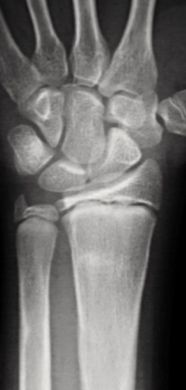

B. Fracturas diafisarias de radio o cúbito no desplazadas (15-18%):

Se pueden tratar de forma conservadora en la mayoría de los casos mediante reducción y estabilización con un yeso braquio-antebraquial (3-5 semanas). La limitación en la pronación y supinación es la complicación más temida y se debe a consolidaciones viciosas, más frecuentes tras una fractura de antebrazo proximal (Figura 12).

Figura 12: a, b-Fractura metafiso-diafisaria distal tratada de forma conservadora donde se aprecia una consolidación viciosa con acortamiento del radio que limitaba la prono-supinación. c, d- Osteotomía correctora con aporte de injerto y osteosíntesis.